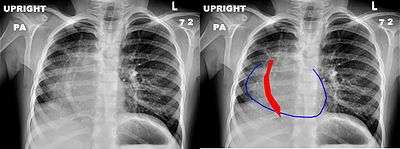

Scimitar syndrome, or pulmonary venolobar syndrome, is a rare congenital heart defect characterized by anomalous venous return from the right lung (to the systemic venous drainage, rather than directly to the left atrium).[1] This anomalous pulmonary venous return can be either partial (PAPVR) or total (TAPVR). The syndrome associated with PAPVR is more commonly known as Scimitar syndrome after the curvilinear pattern created on a chest radiograph by the pulmonary veins that drain to the inferior vena cava.[2] This radiographic density often has the shape of a scimitar, a type of curved sword.[2]

The anomalous venous return forms a curved shadow on chest x-ray such that it resembles a scimitar. This is called the Scimitar Sign. Associated abnormalities include right lung hypoplasia with associated ()dextroposition of the heart, pulmonary artery hypoplasia and pulmonary sequestration.